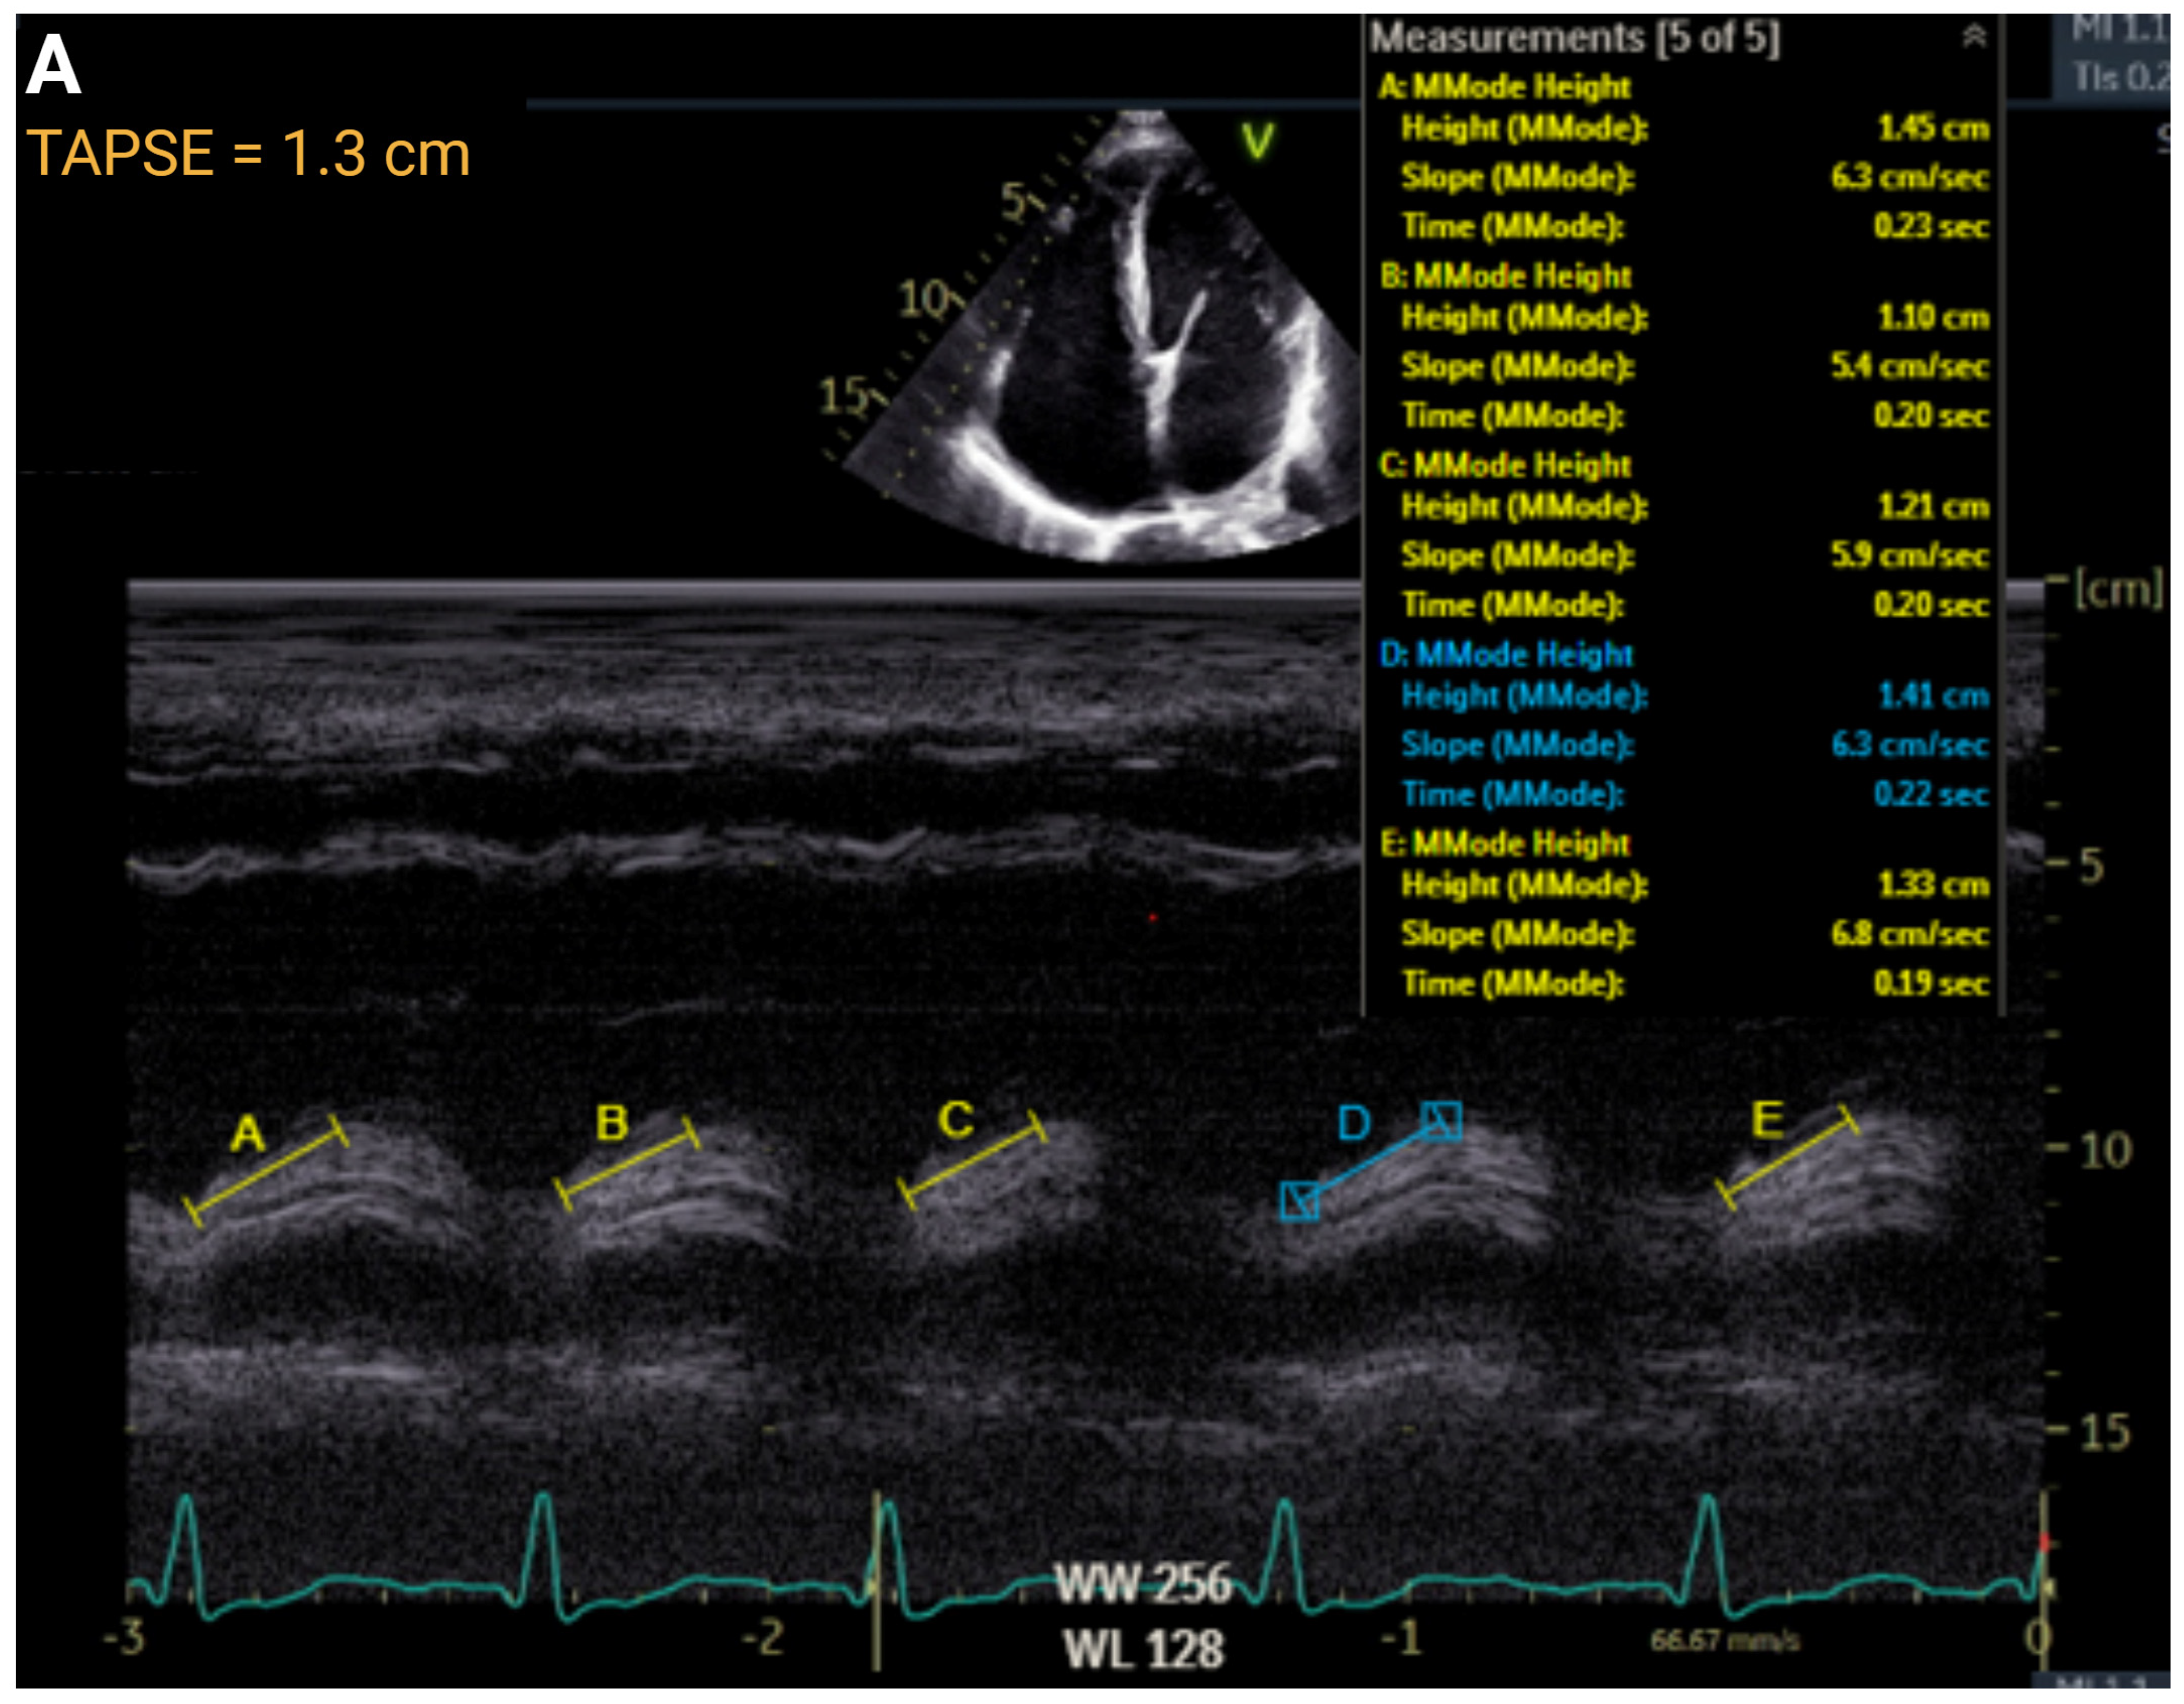

| Right Ventricular Systolic Function | ||||||

| TAPSE, cm | >1.7 | ≤1.7 to ≥1.3 | ≤1.3 to >1.0 | ≤1.0 | r = 0.45 to 0.62 | AUC = 0.74 |